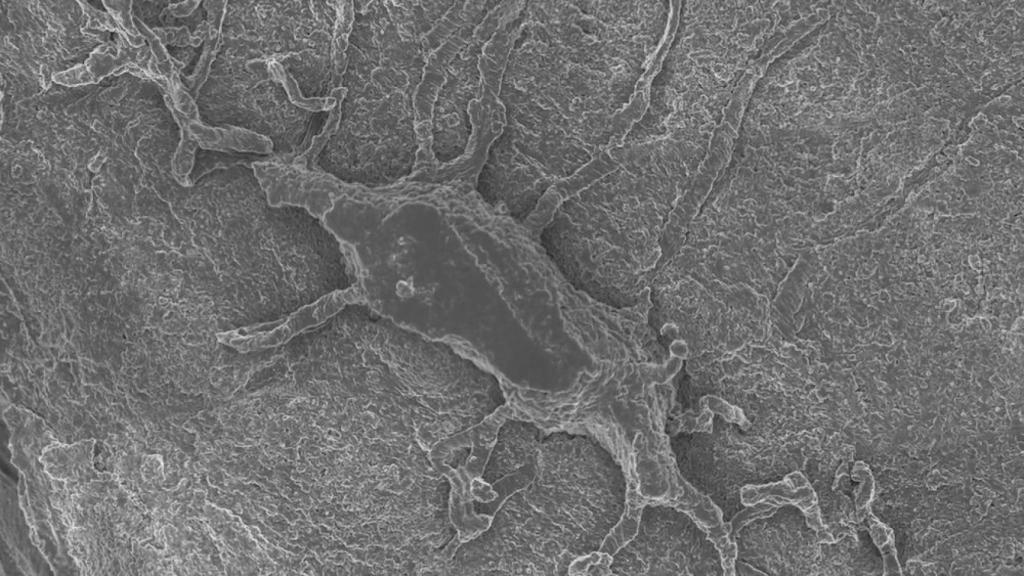

La app en si funciona exactamente igual que Google Maps, con la capacidad de ampliar poco a poco la imagen inicial del cuerpo, llegando a fotografías de microscopio electrónico con una escala de micrómetros; tiene sentido usar la tecnología de Maps, ya que hay muchas similitudes en la gran cantidad de datos e imágenes en alta resolución entre el planeta Tierra y el cuerpo humano.

La profesora Melissa Knothe Tate, líder del proyecto, asegura que esta tecnología permitirá a los científicos llegar desde una imagen de todo el cuerpo a células individuales, para así obtener una imagen más clara de cómo funcionan aspectos como la nutrición de las células, de cómo se mueven y cómo se afectan entre sí en el gran conjunto de las cosas, además de explorar la relación entre el sistema circulatorio, los huesos, el sistema linfático y los músculos.